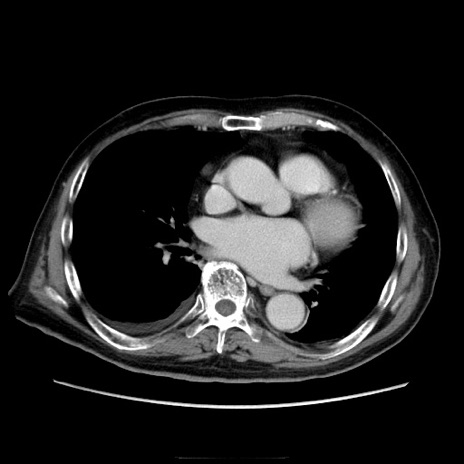

症例21(横断像)

【症例】70歳代男性

【主訴】腹痛

【現病歴】肝硬変・肝細胞癌にてかかりつけの方。約9時間前に食後より腹痛出現。症状が徐々に増悪し、嘔吐出現したため来院。

【既往歴】肝硬変、肝細胞癌(RFA、TACE後)

【身体所見】意識清明、表情苦悶様、BT 36℃、BP 129/78mmHg、P 88bpm、SpO2 97%(RA)、右上腹部から心窩部にかけて圧痛あり、反跳痛なし、筋性防御あり。

【データ】WBC 5800、CRP 0.16